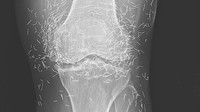

Belum lama ini heboh sebuah temuan dokter terkait ratusan benang 'susuk' emas di lutut seorang pasien wanita 65 tahun di Korea Selatan. Rupanya benang-benang emas itu masuk ke tubuh dari sesi akupuntur yang dijalaninya. (Foto: The New England Journal of Medicine)

Akupuntur dengan benang emas memang populer di Korea Selatan, karena dianggap bisa mengobati osteoarthritis maupun artritis reumatoid. Namun, hingga saat ini belum ada bukti medis berkaitan dengan efektivitas akupuntur dengan masalah kesehatan tersebut. (Foto: The New England Journal of Medicine)